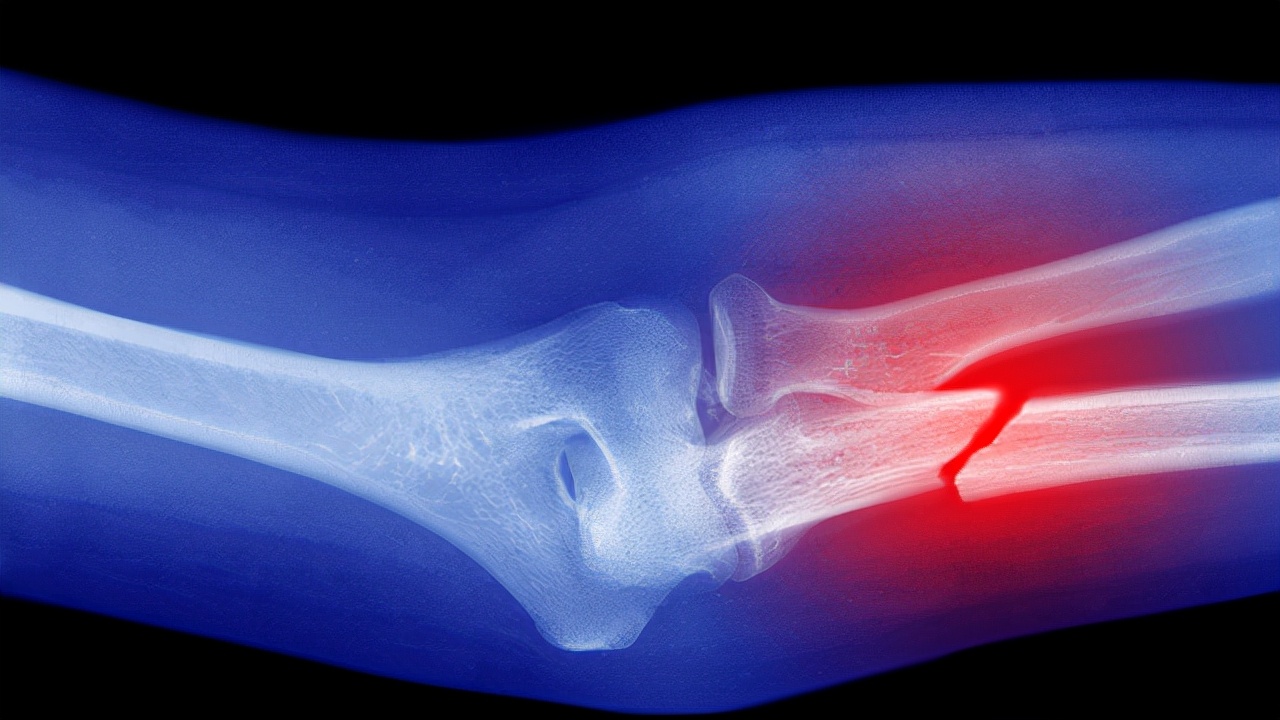

骨质疏松是一种以骨量降低或丢失、骨组织微结构破坏、骨脆性增加为主的代谢性疾病,非常容易导致患者出现骨折,而引起骨质疏松的原因里面,日照减少、维生素D缺乏等引起的缺钙,是很重要的原因之一。

骨质疏松性骨折,做完手术是不是就一劳永逸了呢?随着老龄化社会的到来,骨质疏松越来越多地出现在我们骨折的病人当中,骨质疏松性骨折做完手术之后,我们还需要怎么治疗?